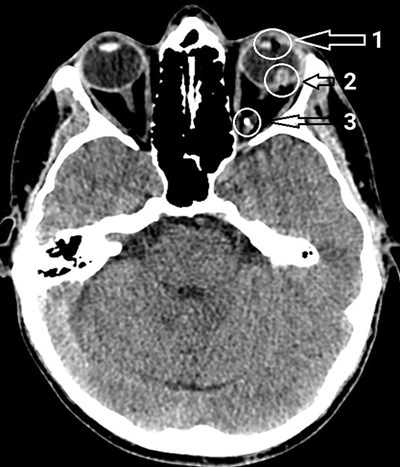

CT scan from case one, annotated: Arrow 1 (top) indicates a gap in the lens of the left eye, which has been bisected by the pellet; arrow 2 (middle) indicates a break in posterior pole of the eye, where the pellet passed through the retina and the sclera; arrow 3 (bottom) indicates the pellet, lying posteriorly in the orbit.